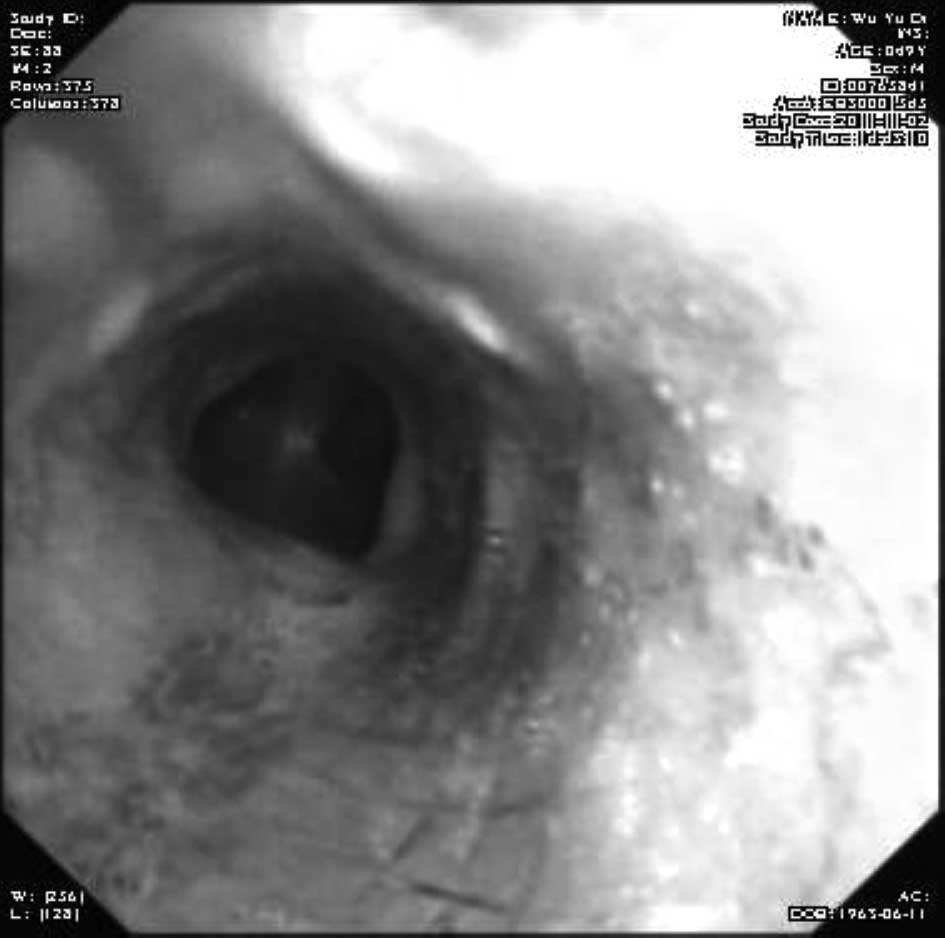

Emergency management of a patient with severe airway obstruction resulting from poorly differentiated thyroid carcinoma: A case report

We present a case of a life-threatening almost complete airway obstruction resulting from poorly differentiated thyroid carcinoma in a 48-year-old male. Airway obstruction may lead to unexpected mortality by suffocation and patients with poorly differentiated thyroid carcinoma usually have a fast deterioration and fatal outcome. In the case presented, we describe a safe and effective treatment strategy. Assisted by femoro-femoral cardiopulmonary bypass oxygenation, a tracheal stent was implanted successfully. Following surgery there were no complications, and chemoradiotherapy resulted in the relief of obstructing symptoms and improved the quality of life of the patient. This case indicates that femoro‑femoral cardiopulmonary bypass provides adequate oxygen support to undergo further management and that tracheal stent implant is an effective emergent measure to relieve severe airway obstruction in patients with poorly differentiated thyroid carcinoma.